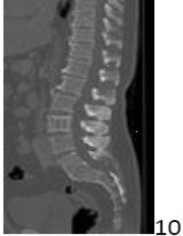

8. # The finding at L3 in the sagittal CT scan shown in Figure 10 is characteristic of which of the following conditions?

DISCUSSION: The L3 vertebral body shows the classic vertical striations of a vertebral hemangioma. On axial images, these would appear as a collection of bony spots as they are seen endon. Paget's disease may have areas of sclerotic trabeculae but the vertebrae appear square and enlarged with thickened cortex and demonstrate no organization in the mineral density. Giant cell

tumors are more lytic and locally destructive. Metastatic disease can be lytic or sclerotic but does not organize in this pattern. Similarly, chordoma does not have this organization. Chordomas more commonly occur in the sacrum, but may occur in the lumbar vertebrae. Prefer Res is 2.